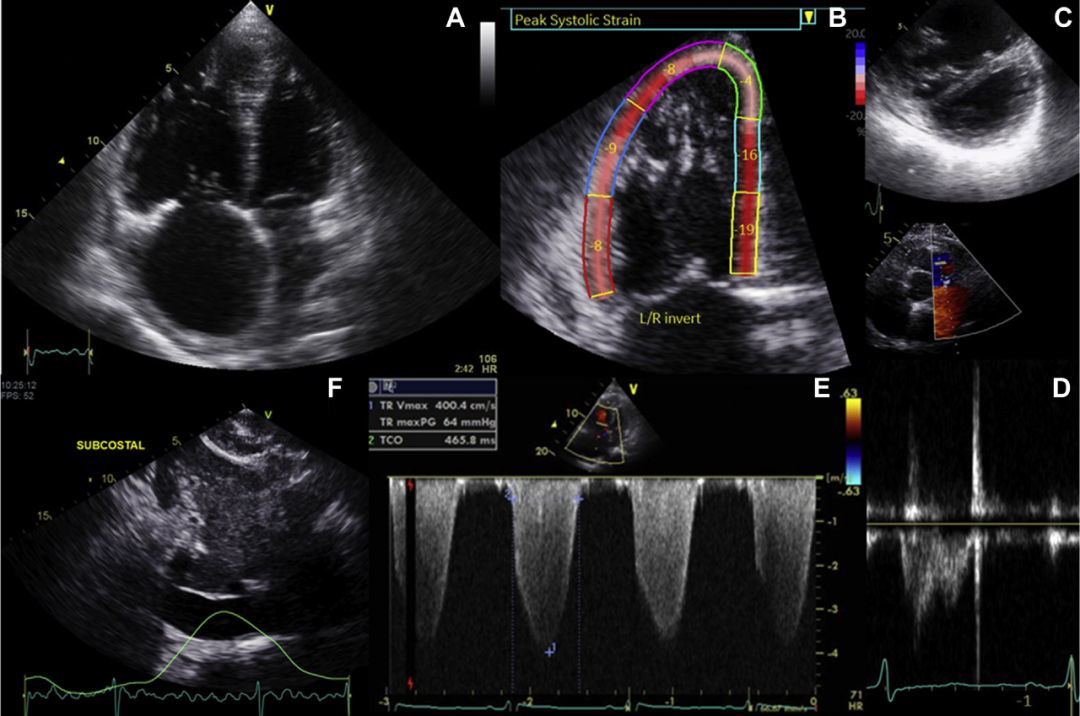

圖1 超聲心動圖對肺動脈高壓的評估和預測。(A)心尖四腔切面顯示右心房和右心室擴大。(B)測量右心室應變。(C)胸骨旁短軸切面顯示室間隔移位。(D)肺流出速度收縮中期切跡。(E)三尖瓣反流估測肺動脈收縮壓。(F)肋下視圖顯示下腔靜脈擴張。

2.推薦對疑似PH患者進行完整的超聲心動圖評估,包括使用三尖瓣返流速度(TRV)評估肺動脈收縮壓(sPAP)、測量下腔靜脈大小和吸氣塌陷程度,以及評估PH的“繼發性”癥狀,如右心房(RA)或右心室(RV)增大,RV肥大、間隔變平、和RV功能障礙(強烈推薦,中等質量證據)。

1. 推薦采用經胸超聲心動圖對所有臨床疑似 PH 或不明原因呼吸困難患者進行初步評估(強烈推薦,中等質量證據)。

4. 推薦PH患者應接受基線和隨訪超聲心動圖檢查,測量收縮期PAP、RA大小、三尖瓣返流嚴重程度以及心包積液存在/嚴重程度。此外,應使用三尖瓣環平面收縮期偏移、運行速度(S’)或 RV心肌性能指數,在具有合適設備和專業知識的實驗室中,推薦使用二維斑點追蹤游離壁應變方法(強烈推薦,中等質量證據)。